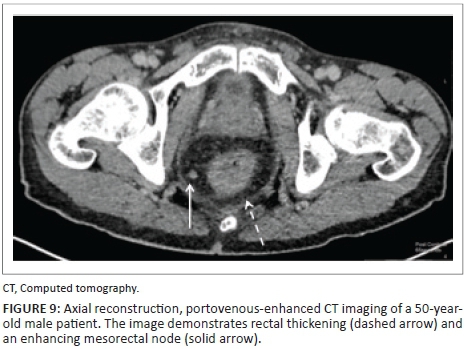

Portovenous-enhanced CT is the preferred imaging modality, with 80% of patients with disseminated disease demonstrating enhancing lymph nodes.15 The masses most commonly appear polypoid (< 3 cm), although larger masses are possible.

Figures 9 and 10 demonstrate a 50-year-old male patient, with CD4 count of 320 cells/μL at initial presentation, with rectal thickening and an enhancing mesorectal node. The diagnosis of rectal KS was made upon transrectal biopsy.